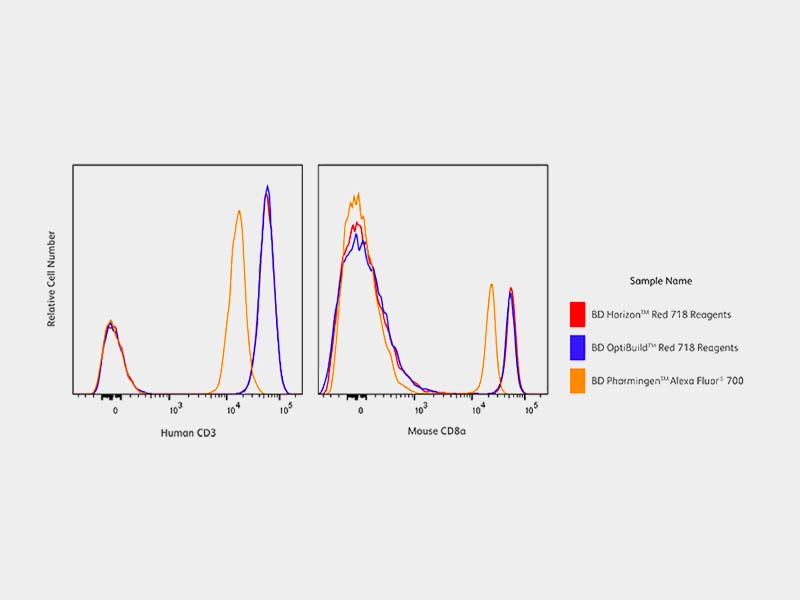

Amazon.com: Optical Quantum Blue AZO CD-R 700MB 52X Shiny, BD Horizon Red 718,

BD Horizon Red 718, Meta Horizon C-Line Cloud Breaker - Gannon Buhr dna SeriesAlbion Presents「幻想の庭」Vol.2の特別CD-R。CAPSULE メトロパルス Amazon.co.jp限定盤。Albion Presents「幻想の庭」Vol.2 配布- 形式: CD-R- 収録曲: 1. Castrum(スタジオ Ver.) 2. 導かれた幻想へ(スタジオ Ver.)ご覧いただきありがとうございます。WEST. A.H.O. 初回盤A、初回盤B、通常盤。Rakshasa/destrose/Octaviagrace/ジャパメタ